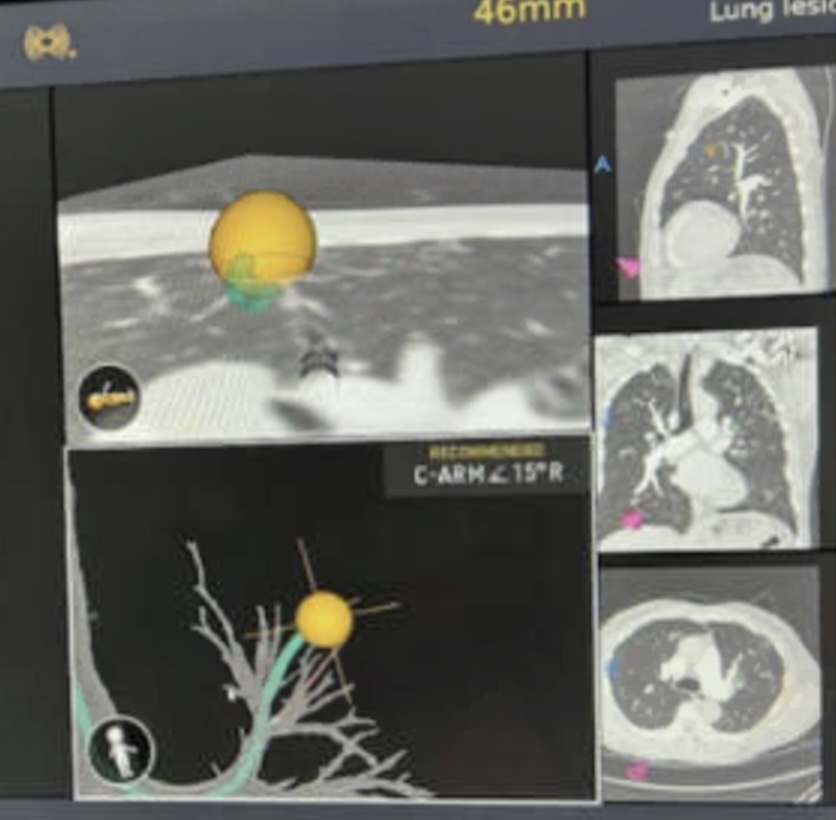

A multicenter prospective study of robotic-assisted bronchoscopy shows that RAB-guided sampling of peripheral pulmonary lesions compares favorably with results from sizable nonrobotic #bronchoscopy studies.

Read more in the August #JournalCHEST issue: hubs.la/Q03Cql920